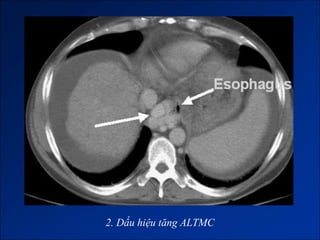

Dấu hiệu tăng ALTMC

Dấu hiệu tăng ALTMC– giả hạch mạc treo

2. Dấu hiệu tăng ALTMC